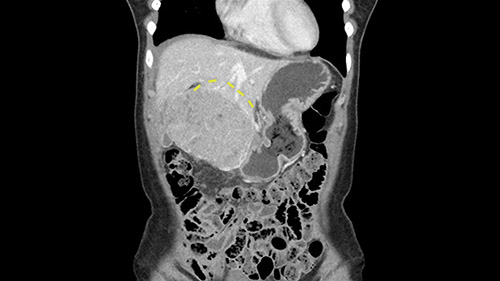

So if we look at the CT scan, on the axial, it’s a larger lesion. It’s about 6 or 7 or 8 centimeters. So it does look a bit threatening in terms of its resectability but if you really drill down deeply into the anatomy, and I think the coronal [imaging] is even better, you can see that the entire mass is on the patient’s left side of the falciform ligament. So it’s really only a left-sided tumor and not even really a left-sided tumor because Segment 4 is uninvolved anatomically.

As I review the CT scan, we have both arterial and venous phases, the tumor is obvious. But I’ll start by saying that the liver itself does not appear to be cirrhotic to my eye. It’s got a normal contour and allied to that, that I do not see evidence of portal hypertension. The spleen is normal, there’s no collateral vessels. The tumor itself, I measured maximally at about 11 centimetres in diameter and I’m told the alpha fetoprotein is very high (over 10000), which is entirely consistent with this being a solitary hepatocellular carcinoma that is very exophytic. It seems to emanate off the inferior margin of Segment 3 (because that’s the falciform). I’ll start by saying that this is not transplantable. The tumor exceeds our guidelines for transplantation, but it's likely resectable based on normal liver and no portal hypertension.

So the issue with regards to resection. A left sided tumor. I believe I can see the falciform ligament right here so we’re looking at a resection of Segments 2, 3 of the left lobe of the liver. The left portal vein is right there. I think we’ll be wiser to take the left portal vein and therefore get well into Segment 4 and do a left hemihepatectomy. Certainly, one does not need to take the middle hepatic vein; it’s miles from the tumor.

The other thing I would do in this case is to certainly to assess the coronal phase as we can see in the coronal phase, this tumor looks like it's growing from Segment 3, and again I don’t think there’s involvement of the right side of the liver or even on Segment 4.